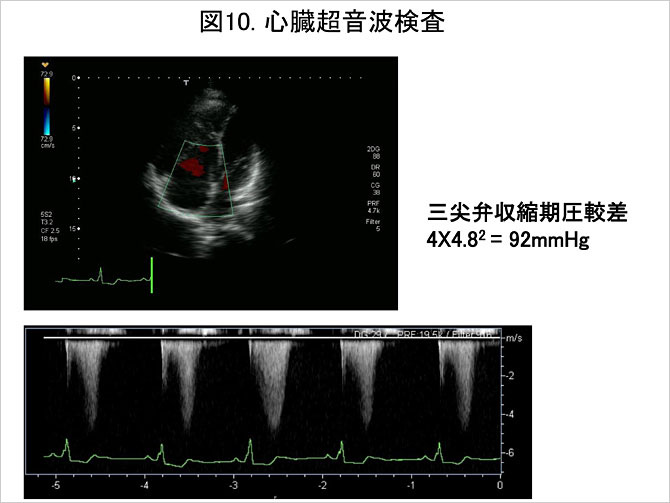

(6)心臓超音波検査 (図10)

心臓超音波検査は肺循環動態の評価やフォローアップにおける肺動脈圧の指標を提供する重要な検査である. 右室・右房の肥大および拡大に加え, 心室中隔の左室側への圧排や奇異性運動などが観察される. また,ドップラー法応用により, 三尖弁および肺動脈弁での逆流波の流速測定から, 弁前後での圧較差の測定および収縮期肺動脈圧の推定が可能である. また心エコーは先天性心疾患に伴う肺高血圧症および各種心疾患に伴う後毛細血管性肺高血圧症を否定する意味でも不可欠の検査といえる.